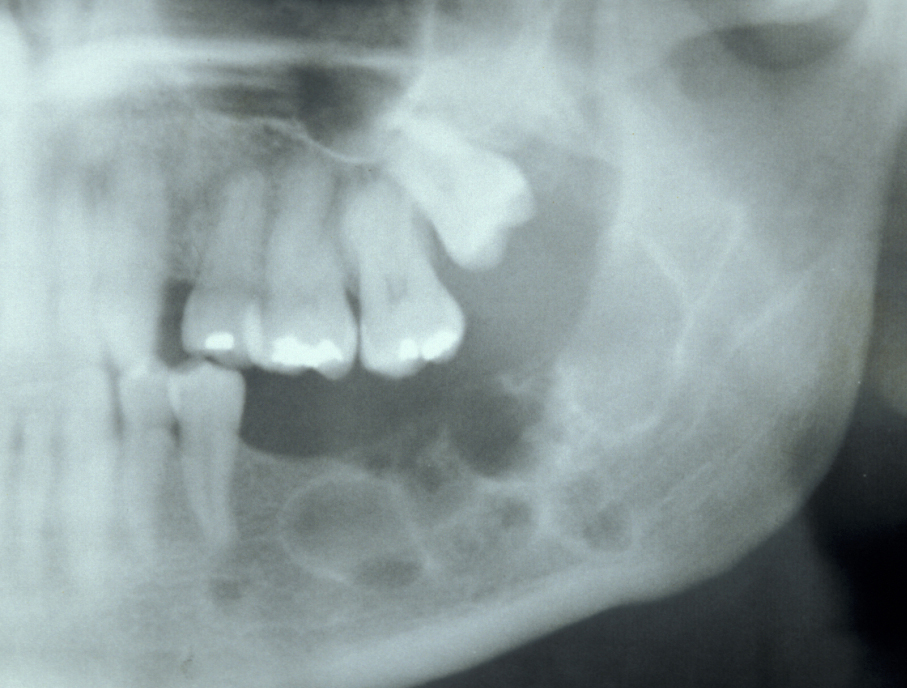

Unicystic ameloblastoma is a cystic swelling distinguished by resorbing adjacent tooth roots: histologically the lesion is an ameloblastoma but it has predominantly fluid contents. Figure 4 shows an example.

Figure 6: Unicystic amelobastoma resorbing tooth roots.